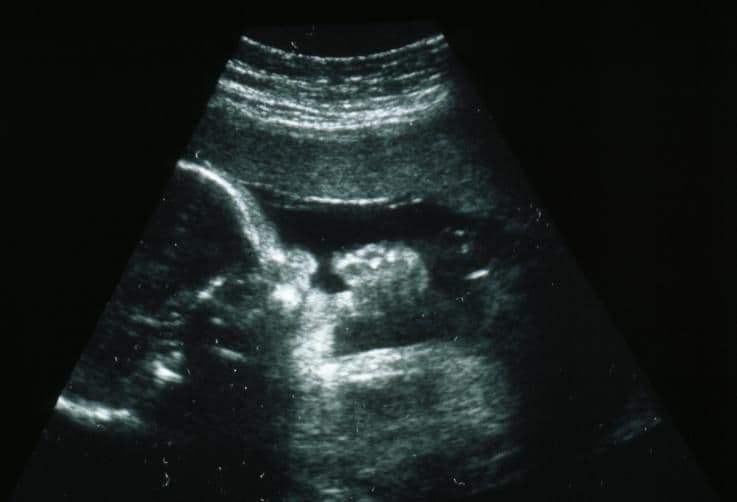

This 2D ultrasound has captured the moment that the baby is sucking his thumb. Your baby is gradually learning to co-ordinate this complex activity with breathing movements even though surrounded not by air but by the amniotic fluid.

Inside the uterus your baby is already practising the suckling reflex, which will enable him to feed when he’s born.

The suckling reflex is present earlier in pregnancy but it is known from assessing premature babies that it’s usually not until around this time that the baby is strong and co-ordinated enough to suckle with ease. Your baby regularly practises suckling and this, in combination with the rooting reflex, will enable him to feed.